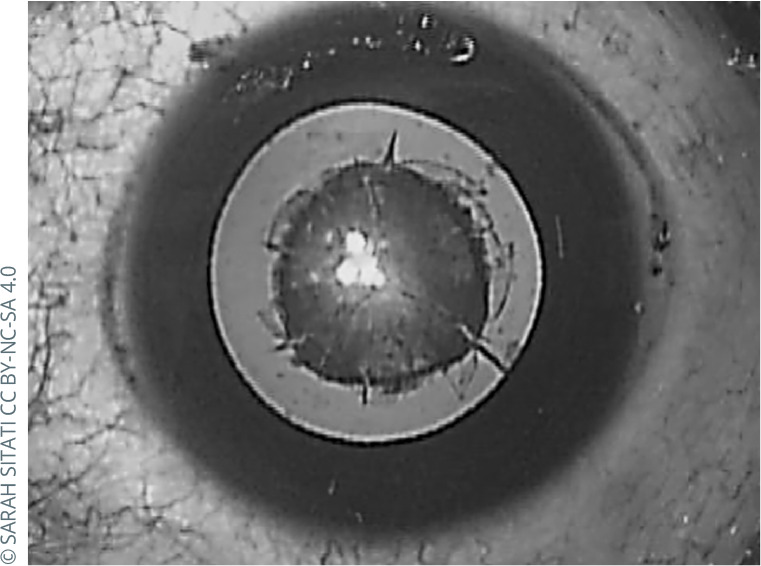

Recognising and managing bilateral cataracts in children.

Sarah Sitati